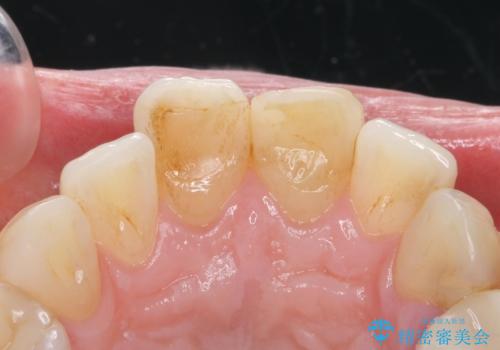

- 前歯の変色を主訴に来院されました。

変色に対してはかぶせ物で周囲の歯との色調を合わせます。

根管治療についてご説明をし、右上の1本だけ再根管治療を行うこととなりました。